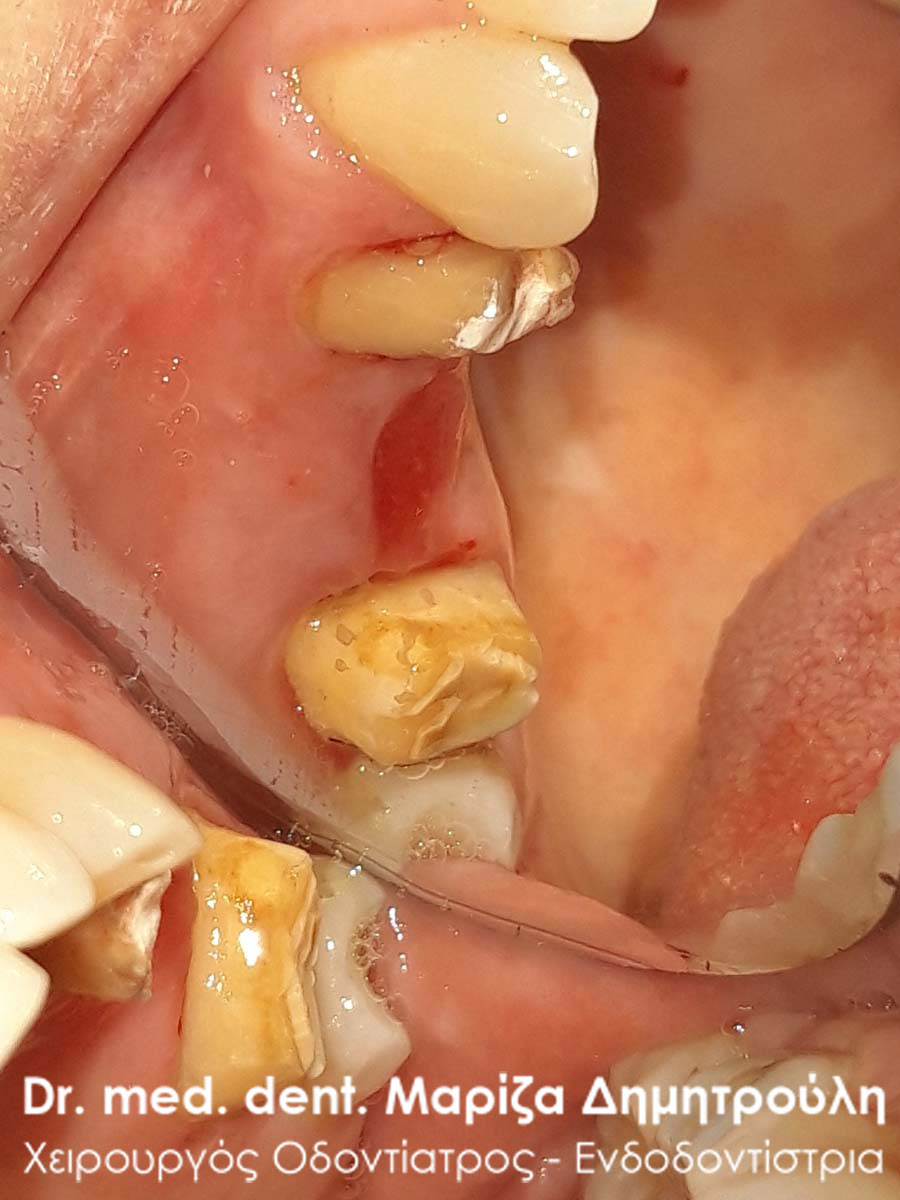

Περιστατικό – Ολοκεραμική στεφάνη / θήκη ζιρκονίου στον άνω αριστερό γομφίο

Η ασθενής επισκέφτηκε το ιατρείο μας γιατί πονούσε στον πρώτο άνω αριστερό γομφίο. Η κλινική και ακτινογραφική εξέταση φανέρωσε την αναγκαιότητα απονεύρωσης του δοντιού. Μετά το πέρας της ενδοδοντικής θεραπείας και εφόσον το οδοντικό έλλειμα ήταν μεγάλο, κρίθηκε απαραίτητη η προστασία του απονευρωμένου δοντιού με ολοκεραμική θήκη.

Αρχική κλινική εικόνα του δοντιού με το προσωρινό σφράγισμα απονεύρωσης